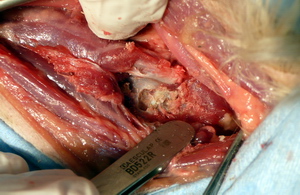

Fijación cervical ventral

Agujas roscadas